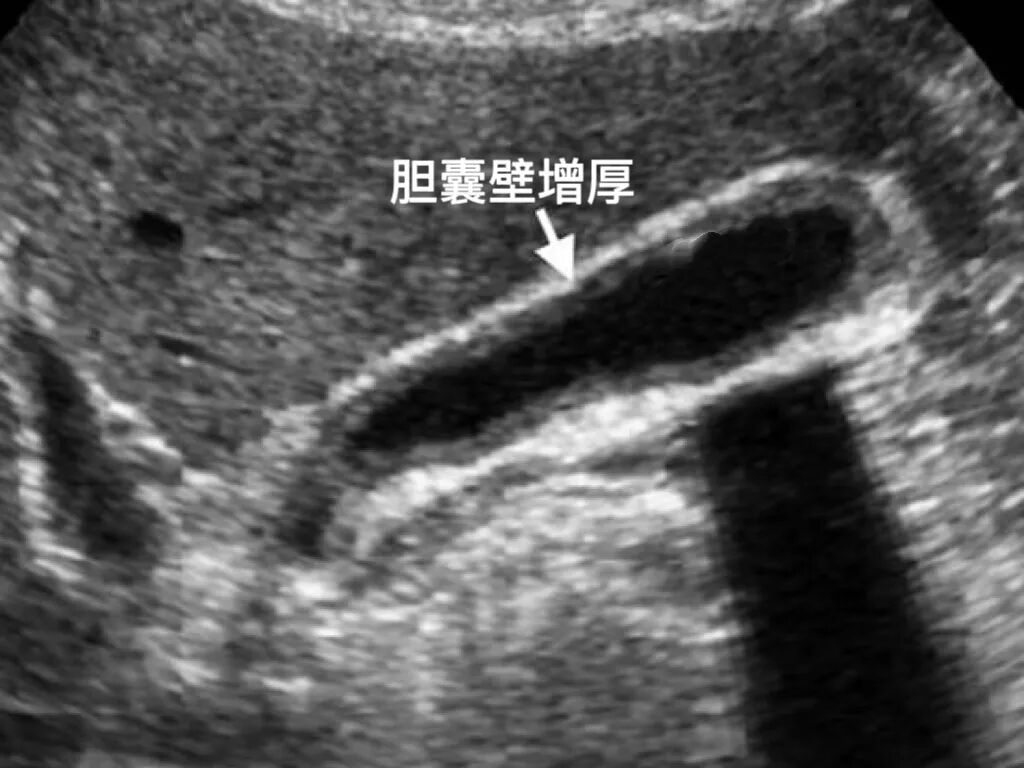

3.慢性胆囊炎影像改变:B超显示胆囊壁厚、粗糙或胆囊收缩功能差、胆汁排空不畅等;